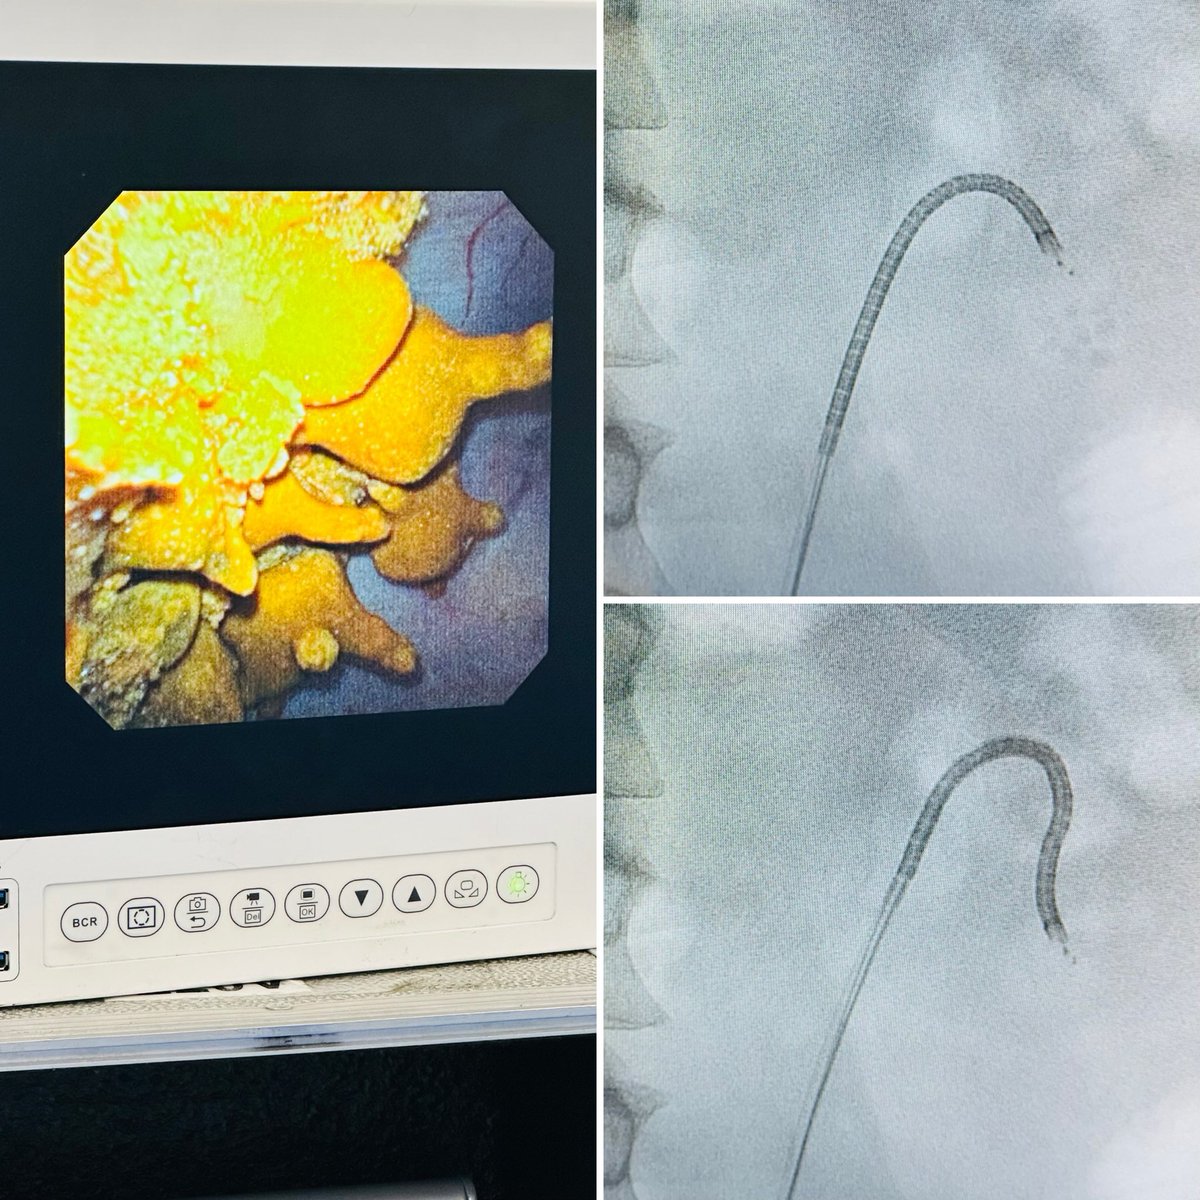

@EAU26 Discussion on next generation DISS technique (ZS procedure)....Happy to b recognised in the EAU stage as ""concept inventor of DISS ""along with @DocGauhar @BAUSurology @Uroweb #EAU26 @AmerUrological @USANZUrology @so_uro #DISS #UroSoMe

Large volume/hard/SH stone : managed by ZS system:: no prestent ;; total stent period of 3weeks: between the stage:: on table visually imaged clearance at Stent removal: @29Arundati32339 @DocGauhar @OTRAXER #EAU26 @sbinhamrii @so_uro #DISS #UroSoMe @BEkidneystone @Endo_Society